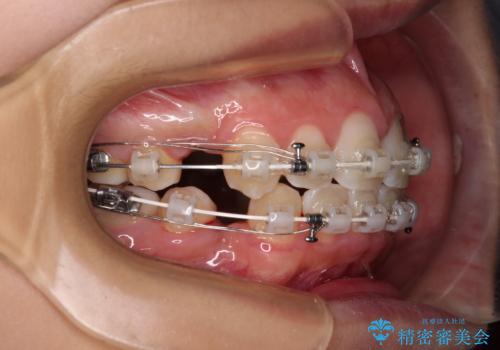

気がつくと唇があいてしまう ワイヤー装置での抜歯矯正

- 口元の突出感で口が閉じにくいとのことで来院された患者様です。

上下左右の第一小臼歯4本を抜歯し、ワイヤー装置での抜歯矯正を行うこととしました。

右側の咬み合わせは、上顎がやや前方位にある状態であったので、通常は補助装置を併用するのですが、高校生ということで補助装置なしで治療を行うこととしました。